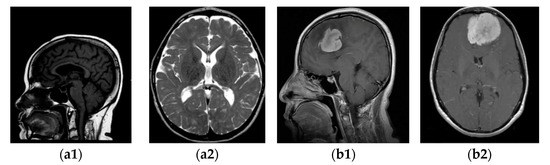

3.1. Brain MRI Kaggle Dataset

3.2. Data Augmentation and Pre-Processing